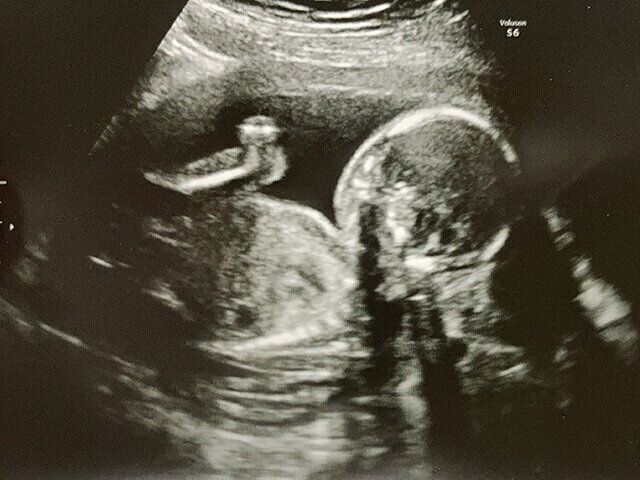

4. 無痛分娩

5. 「あ、泣き声が聞こえない…」出産予定日1カ月前の早産、無痛分娩、新生児仮死…ドタバタ出産体験談